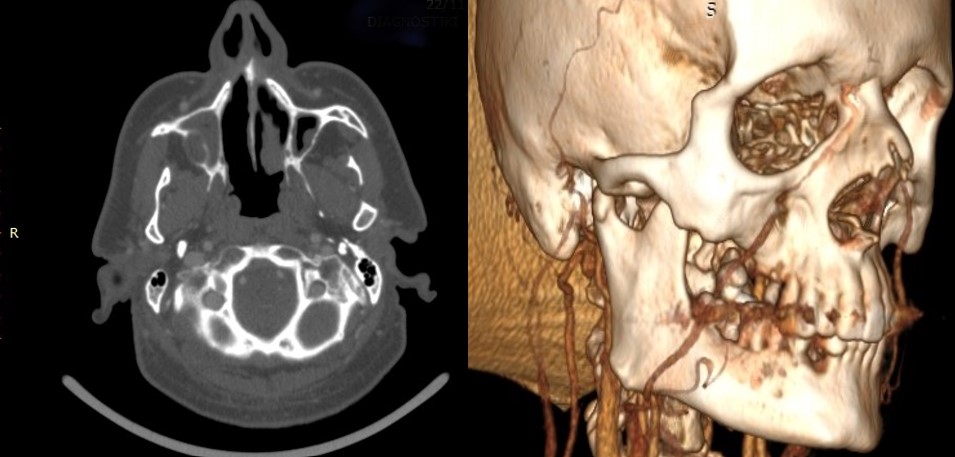

Computed tomography (CT) with intravenous contrast showed a poorly defined osteolytic lesion of the right posterior maxilla that widely involved the maxillary sinus and extended anteriorly to tooth 14 and posteriorly up to the pterygoid process of the sphenoid without infiltrating it (Figure 2). No cervical lymph node pathology was demonstrated on CT of the neck. Magnetic resonance imaging (MRI) demonstrated a relatively high-intensity area within the right maxilla that extended anterioposteriorly for 3 cm from the premolar region to the maxillary tuberosity, cephalocaudally for 2 cm from the pterygoid process of the sphenoid to the alveolar crest, and buccally/palatally for 1.5 cm, widely involving the right maxillary sinus.

OCCs are depicted in CT scans as both well-defined and ill-defined tumors, causing cortical erosion and/or cancellous destruction of the adjacent bone while primarily affecting the soft tissues.4,7,11 MRI shows tumors of heterogeneous intensity, causing gingival inflammation but sparing the extrinsic muscles, when located at the tongue. Panoramic radiographs, used as a screening tool, usually reveal ill-defined, irregular osteolytic radiolucent lesions infiltrating the cortical and cancellous bone and involving anatomic structures, such as the nasal floor, sinus walls, or mandibular canal.5 In this case, the tumor had infiltrated not only the adjacent bone but also the right maxillary sinus floor, extending widely into the sinus.